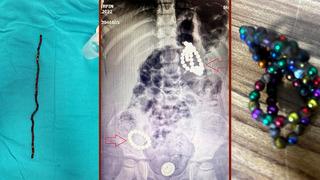

Bu oyuncak bir ölüm tuzağı! Herkesi çok şaşırtan vaka: 3 yaşında, karnında 66 adet mıknatısla aylarca yaşamış! Tehlikeye karşı uyarı: İç organlarını deliyor

İstanbul’da yaşayan Mahmut ve İsmigül Nesim çiftinin 3 yaşındaki kızları Berfin, mide ve bağırsaklarında tam 66 adet manyetik boncukla aylarca yaşadı. Mide bulantısı ve kusma şikayetiyle hastaneye kaldırılan küçük kız, 5 saat süren kritik bir ameliyatla sağlığına kavuştu. Çocuk Cerrahi Kliniği’nden Opr. Dr. Mehmet Çakmak, bu vakanın şimdiye kadar karşılaştıkları en yüksek sayıda mıknatıs boncuk içeren ve en riskli vakalardan biri olduğunu söyledi. Detaylar haberimizde...